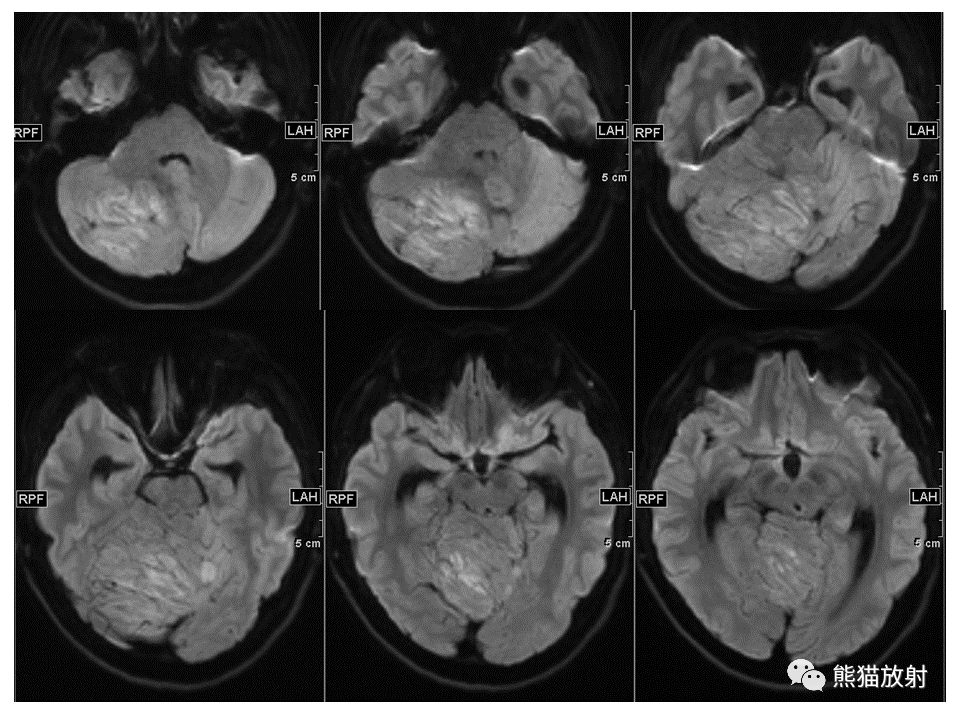

【PPT】小脑发育不良性神经节细胞瘤 VS 成人型髓母细胞瘤-2